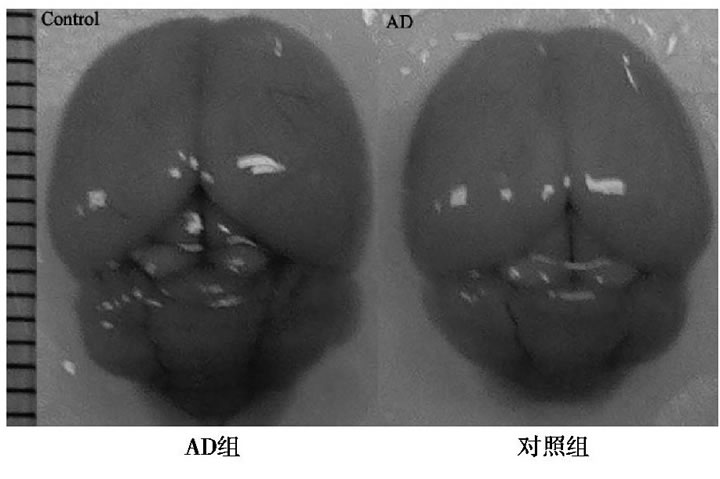

2.1 AD和對照組全腦圖

與對照組比較, AD小鼠完整腦組織表面泛白、無血色, 血管明顯減少, 表明D-半乳糖聯(lián)合三氯化鋁已經(jīng)對小鼠的腦組織形成退行性損傷。見圖1。

圖1 AD組和對照組小鼠全腦圖